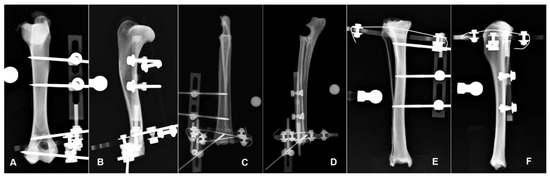

3.1. Humerus

| 1 | AP | 1958.33 | 1958.33 | 1838.28 | 120.06 | 1.00 (100) | 1.07 | 107 | 1.07 | 107 | ||

| 1 | ML | 1888.4 | 1870.82 | 1713.13 | 157.69 | 1.01 (101) | 1.1 | 110 | 1.09 | 109 | ||

| 2 | AP | 1966.67 | 1966.67 | 1581.47 | 385.2 | 1.00 (100) | 1.24 | 124 | 1.24 | 124 | ||

| 2 | ML | 1404.31 | 931.4 | 752.07 | 179.33 | 1.51 (151) | 1.87 | 187 | 1.24 | 124 | ||

| 3 | AP | 1969.76 | 1969.76 | 1543.45 | 426.3 | 1.00 (100) | 1.28 | 128 | 1.28 | 128 | ||

| 3 | ML | 1227.68 | 715.65 | 583.74 | 131.92 | 1.72 (172) | 2.1 | 210 | 1.23 | 123 | ||

| 4 | AP | 1824.27 | 1824.27 | 1627.47 | 196.8 | 1.00 (100) | 1.12 | 112 | 1.12 | 112 | ||

| 4 | ML | 1421.43 | 854.83 | 745.95 | 108.88 | 1.66 (166) | 1.91 | 191 | 1.15 | 115 | ||

| 5 | AP | 1879.15 | 1879.15 | 1618.41 | 260.74 | 1.00 (100) | 1.16 | 116 | 1.16 | 116 | ||

| 5 | ML | 1353.75 | 1138.71 | 1053.82 | 84.89 | 1.19 (119) | 1.28 | 128 | 1.08 | 108 | ||

| 6 | AP | 1779.92 | 1779.92 | 1553.29 | 226.63 | 1.00 (100) | 1.15 | 115 | 1.15 | 115 | ||

| 6 | ML | 1315.31 | 839.31 | 724.42 | 114.89 | 1.57 (157) | 1.82 | 182 | 1.16 | 116 | ||

| Median | AP | 1918.74 | 1918.74 | 1599.94 | 243.68 | 1 | 1.15 | 115.35 | 1.15 | 115.35 | p = 0.0143 | |

| ML | 1379.03 | 893.12 | 749.01 | 123.4 | 1.54 | 1.84 | 184.15 | 1.15 | 115.23 | p = 0.0143 | ||

| (range) | AP | (1779.92–1969.76) | (1779.92–1969.76) | (1543.45–1838.28) | (120.06–426.30) | (1.00–1,00) | (1.07–1.28) | (106.53–127.62) | (1.07–1.28) | (106.53–127.62) | ||

| ML | (1227.68–1888.40) | (715.65–1870.82) | (583.74–17,134.13) | (84.89–179.33) | (1.01–1.72) | (1.10–2.10) | (110.23–210.31) | (1.08–1.24) | (108.06–123.84) |